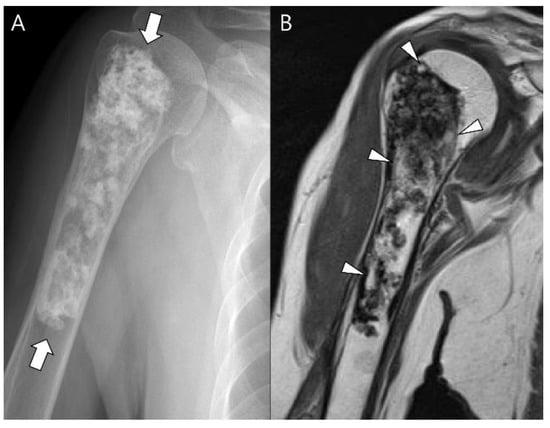

- Capanna, R.; Bertoni, F.; Bettelli, G.; Picci, P.; Bacchini, P.; Present, D.; Giunti, A.; Campanacci, M. Dedifferentiated chondrosarcoma. J. Bone Jt. Surg. Am. 1988, 70, 60–69. [Google Scholar] [CrossRef]

- Daly, P.J.; Sim, F.H.; Wold, L.E. Dedifferentiated chondrosarcoma of bone. Orthopedics 1989, 12, 763–767. [Google Scholar] [CrossRef] [PubMed]

- Mercuri, M.; Picci, P.; Campanacci, L.; Rulli, E. Dedifferentiated chondrosarcoma. Skelet. Radiol. 1995, 24, 409–416. [Google Scholar] [CrossRef]

- Grimer, R.J.; Gosheger, G.; Taminiau, A.; Biau, D.; Matejovsky, Z.; Kollender, Y.; San-Julian, M.; Gherlinzoni, F.; Ferrari, C. Dedifferentiated chondrosarcoma: Prognostic factors and outcome from a European group. Eur. J. Cancer 2007, 43, 2060–2065. [Google Scholar] [CrossRef]

- Littrell, L.A.; Wenger, D.E.; Wold, L.E.; Bertoni, F.; Unni, K.K.; White, L.; Kandel, R.; Sundaram, M. Radiographic, CT, and MR Imaging Features of Dedifferentiated Chondrosarcomas: A Retrospective Review of 174 De Novo Cases. Radiographics 2004, 24, 1397–1409. [Google Scholar] [CrossRef]

- Saifuddin, A.; Mann, B.; Mahroof, S.; Pringle, J.; Briggs, T.; Cannon, S. Dedifferentiated chondrosarcoma: Use of MRI to guide needle biopsy. Clin. Radiol. 2004, 59, 268–272. [Google Scholar] [CrossRef]